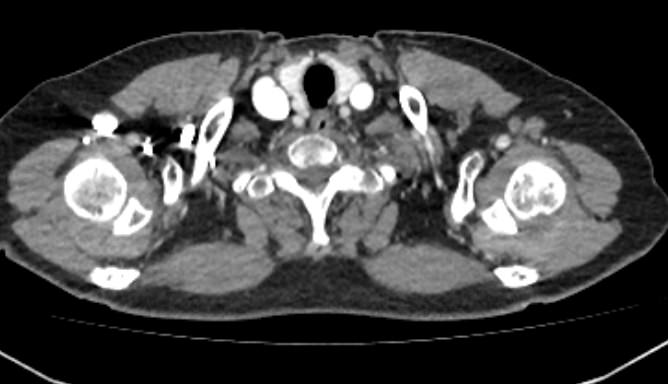

Мультиспиральная компьютерная томография сосудов верхних конечностей (КТ-ангиография) применяется для оценки состояния и функционирования артериальной сосудистой системы руки. При заболеваниях сосудов развивается нарушение кровообращения в руках, что проявляется симптомами ишемии верхних конечностей: боли в мышцах, онемение, бледность и похолодание пальцев рук.

КТ-ангиография позволяет увидеть анатомические особенности строения сосудов рук, выявить врожденные аномалии развития сосудов, диагностировать наличие аневризм, а также сужения просвета сосудов на фоне атеросклероза и других сосудистых заболеваний. КТ применяется в хирургической практике при планировании оперативных вмешательств и в последующем для оценки эффективности хирургического лечения.

Методика КТ-ангиографии основана на использовании ионизирующего излучения и способности органов и тканей организма в разной степени поглощать рентгеновские лучи. Для визуализации сосудистой системы пациенту внутривенно вводится йодсодержащий контрастный препарат.

Контраст способен активно поглощать рентгеновские лучи, благодаря чему сосудистая система хорошо видна на снимках КТ.